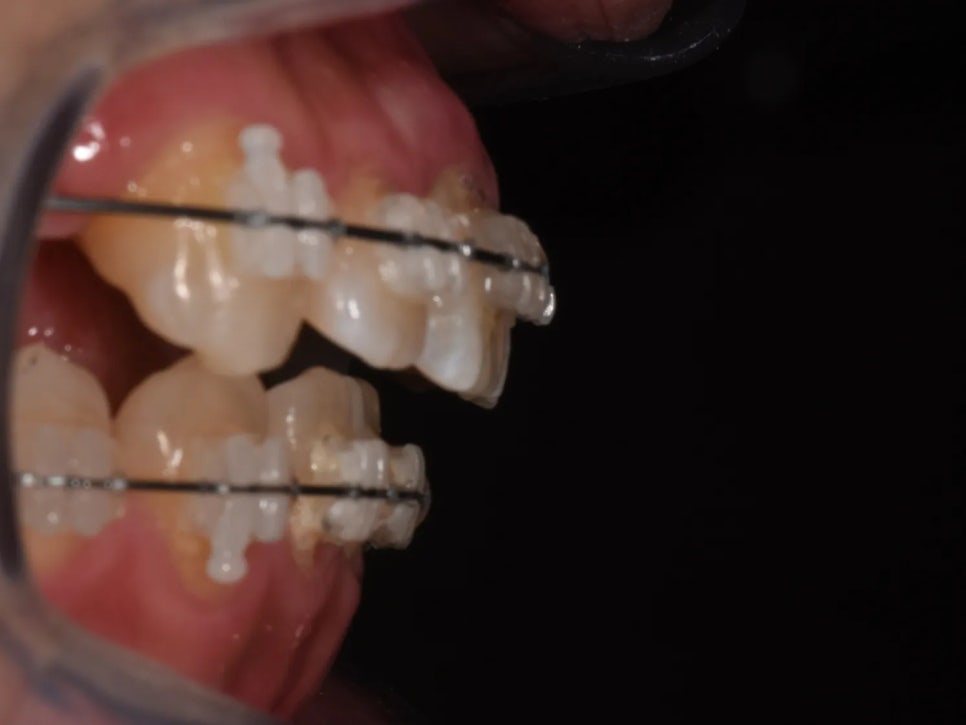

동시에, 정출되면서 바깥쪽(볼 쪽)으로 빠져나가 있던 어금니를 안쪽(입천장 쪽)으로 당기는 작업도 진행하였습니다. 어금니가 제자리에 정확히 위치해야 아래 치아와 정상적으로 맞물릴 수 있기 때문입니다.

정출되면서 바깥쪽으로 빠져나갔던 어금니를 안쪽으로 당겨주는 과정